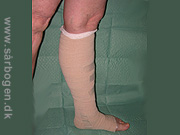

Kompressionbandage

Zoom